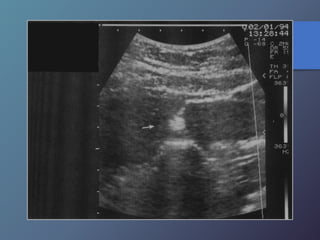

Abscesos Hepáticos Bacterianos

• Extensión directa por vía biliar-portal o

traumática.

• Características ecográficas variables

hipoecoicas.

• Artefactos de reverberación por

presencia de gas.

• Tabiques internos.

• Pared variable desde bien definida a

irregular y gruesa.

Abscesos Hepáticos Bacterianos •Extensión directa por vía biliar-portal o traumática. • Características ecográficas variables hipoecoicas. • Artefactos de reverberación por presencia de gas. • Tabiques internos. • Pared variable desde bien definida a irregular y gruesa.